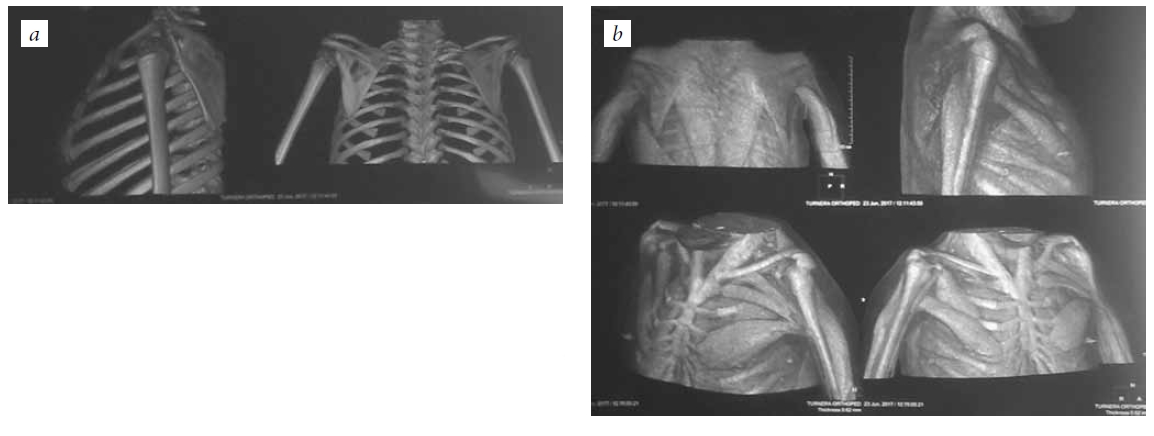

The patients were examined preoperatively and ≥1 year after the intervention. The following indicators were examined in a clinical examination: the amplitude of movements in the elbow joint (active and passive), the strength of the flexor muscles of the forearm and the donor area, and the ability to perform daily activities independently. The amplitude of elbow joint movements was determined using a goniometer. Muscle strength was evaluated on a six-point scale (0–5 points) when moving on a plane, while overcoming gravity, and with manual resistance. BMB was examined via palpation in the position of adduction, extension, and internal rotation of the shoulder. When surgery was planned for children >4 years of age, electromyography (EMG) of the muscles of the flexors and extensors of the forearm and the broadest muscle of the back was performed. Due to the complexity of the neurophysiological study and magnetic resonance imaging in young children, a computed tomography examination of the chest and shoulder in different modes was performed to assess the condition of the muscles of potential donor areas; this enabled a simultaneous understanding regarding the state of soft tissues, bones, and joints of the segment under study (Fig. 1).

Fig. 1. CT scan of the chest and shoulder in different modes for the simultaneous visualization of the soft tissues, bones, and joints of the segment under study: a — visualization of the bones and the joints; b — visualization of the muscles of the shoulder and the chest